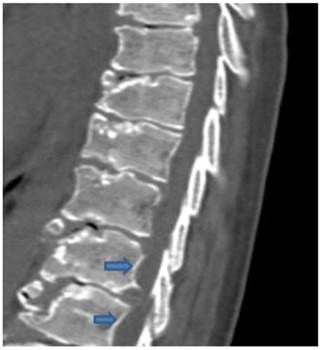

Fig. 3 C-spine x-ray (lateral): disc space narrowing, posterior marginal spurring and degenerative endplate change at C4/5, C5/6 and C6/7. MET and LAS for cervical disc herniation with The NDI assesses the impact of cervical spine pain on a number of activities of daily living.25,26 ... Get Doc

Imaging In Ankylosing Spondylitis Ther Adv Musculoskel Dis